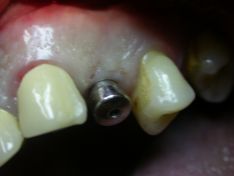

Con un avvitatore manuale si è provveduto a svitare il mounter dall’impianto

ed evidenziare il posizionamento in cresta ed il collo lucido della parte superiore

dello stesso, su’ cui verrà inserita la vite tappo e sutura del lembo mucoperiosteo.

![]() | |

![]() |